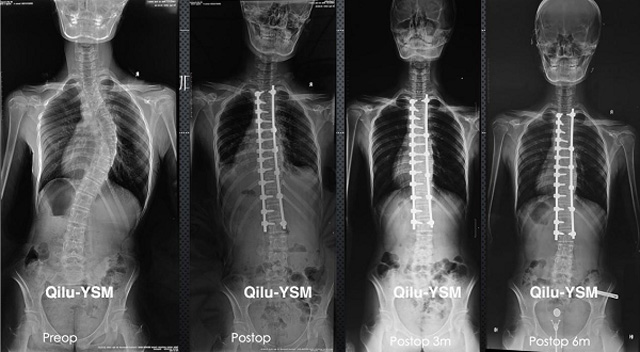

懸吊DR-全電動型機(jī)架DR檢查主要用于胸部、四肢、關(guān)節(jié)、脊柱等,主要檢查肺部炎癥、腫瘤、結(jié)核病、四肢骨關(guān)節(jié)的骨折、四肢關(guān)節(jié)、脊柱外傷等。DR就是X光,是一種數(shù)碼影像,曝光時間很短,攝像量很小,影像質(zhì)量也很好,可以說是一種替代CR的方法。DR檢查有其局限性,需要做CT平掃等檢查,周圍淋巴結(jié)的轉(zhuǎn)移以確定病變的良惡性、范圍、大小、與鄰近組織的關(guān)系。